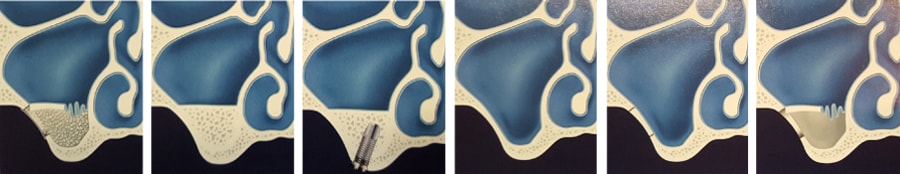

מהו העיקרון של ניתוח הרמת סינוס?

הרופא יפתח, דרך הפה ובצד הלסת העליונה, פתח צד הדומה "לחלון" אל הסינוס המקסילארי ובצורה עדינה וזהירה, ישחרר את הרקמה המרפדת את רצפת הסינוס (שהיא גם תקרת הלסת העליונה). פתיחה זאת נעשית בצורה מכאנית, אך נדרשת הקפדה מיוחדת לא לפגוע או לחרר את אותה הרקמה השבירה באופן מיוחד.

טכנולוגיות חדשניות כמו השימוש בלייזר, מוסיפות בטיחות ויעילות למנתח ולמטופל. הפרדה והרמת ממברנת הסינוס, מיועדות ליצור חלל בו יושתל שתל העצם. על פי רוב, כיום נעשה שימוש בתחליפי עצם מבנק העצם או חומר מינראלי מבעלי חיים, דבר החוסך לרופא ולמטופל פתיחת אתר נוסף. לאחר מילוי החלל, הרופא יניח ממברנת קולגן להגנת שתל העצם ולסגירת החלון. תפירה קלאסית מסיימת את הפרוצדורה.

במידה ובסיס רצפת הסינוס המקורי (לפני השתלת העצם ), מספיק עבה (כלומר מעל 3-4 מ"מ), יותקנו השתלים יחד עם הרמת הסינוס, כך שייקלטו בו זמנית השתלים ושתל העצם. במקרים אחרים כאשר רצפת סינוס דקה במיוחד, התקנת השתלים תדחה לשישה חודשים לאחר ריפוי וקליטת העצם. הטיפול המשולב (הרמת סינוס ושתלים), בהחלט מקצר את תהליך שיקום האזור, אך ההחלטה על מהלך הניתוח, נשארת בידיו של המנתח.